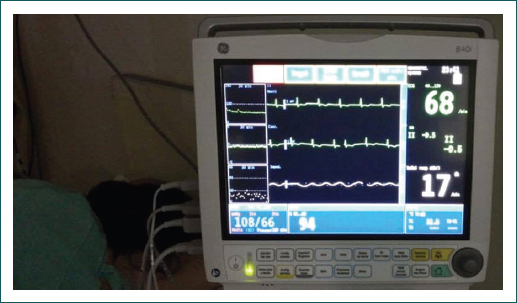

La paciente presentó disminución de la saturación de manera progresiva, llegando a una SpO2 de 84%; la frecuencia respiratoria se mantuvo entre 20-28 rpm (Fig. 2). En este contexto, por hipoxemia persistente, se realizó maniobra de pronación en paciente no intubada con mejoría a los 10 minutos y elevación de la saturación de oxígeno por pulsioximetría hasta 94% (Fig. 3). Esta posición se mantuvo cuatro horas por tolerancia de la paciente. Al encontrar mejoría, se indicó repetir posición prono dos veces al día de cuatro a ocho horas (según tolerancia de la paciente), por cuatro días en total. La paciente presentó mejoría clínica, por pulsioximetría y en la relación PaO2/FiO2, que en supino alcanzó 285 al tercer día posterior a la pronación (Cuadro I). Se realizó nueva PaO2/FiO2, posterior al cuarto día de posición prono con un resultado de 332, y nueva radiografía de tórax tres días después de la maniobra de posición prono, la cual mostró disminución de los infiltrados intersticiales bilaterales (Fig. 4). Se retiró el oxígeno suplementario con SpO2 de hasta 94% al aire ambiente, sin requerimiento de oxígeno suplementario y con una SpO2/FiO2 de 447. Se realizó prueba de caminata de seis minutos con disminución de la SpO2 de 94% a 92%. Se indicó su egreso a los ocho días de hospitalización con signos vitales estables.